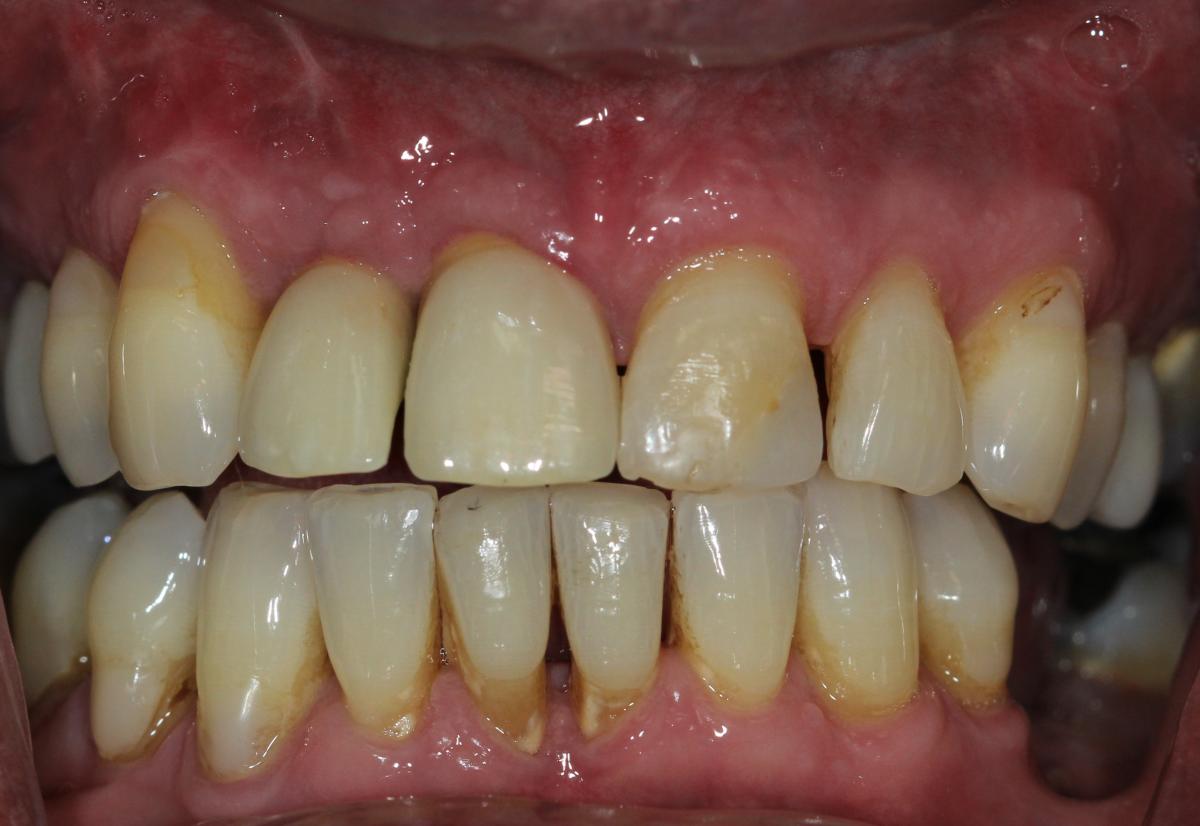

Missing teeth and loose dentures make many people avoid social settings because they are too self-conscious about their appearance. Current dental procedures, however, replace everything from a single missing tooth to a completely missing arch. Ask your dentist or dental specialist about the different dental options that are available to you. Don’t let another day go by without taking this important first step to restoring your confidence and your smile!